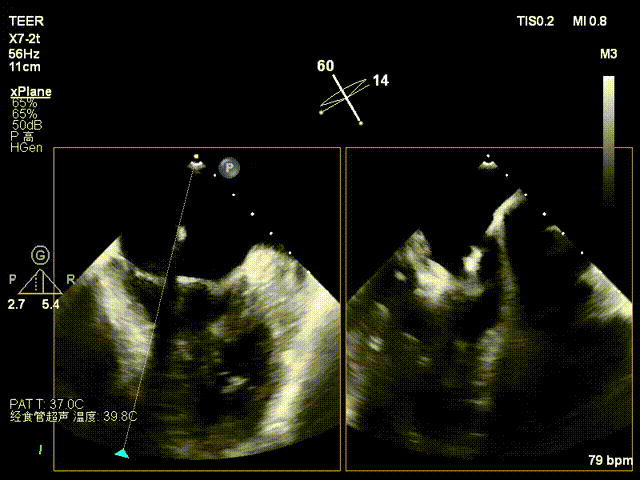

经食道超声检查提示:二尖瓣瓣叶增厚冗长2区后瓣脱垂呈连枷样改变,考虑Barlow’s综合征。评估解剖结构:前叶长度:3.3cm,后叶长度:2.8cm,脱垂宽度:26mm,脱垂高度:19mm,瓣口面积:7.5cm²。

术前影像

X-plane 1区

X-plane 2区

X-plane 2区彩色